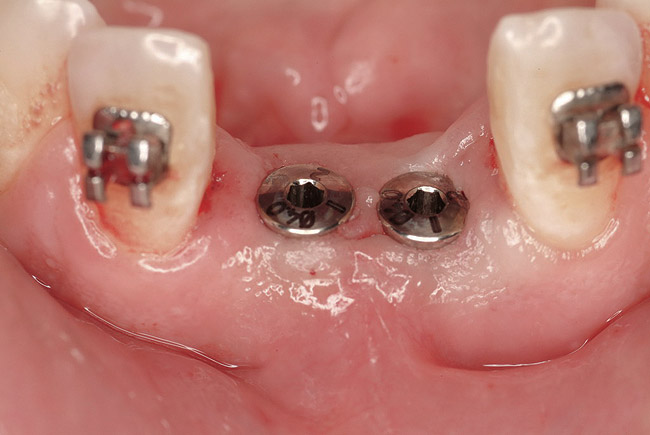

Figure 22  Surgical template, supported by the four remaining teeth and soft tissues. Sequential computer-guided implant placement was used to further stabilize subsequent implant insertions.

Figure 22

Figure 23  Implant placement in the Nos. 7, 8, and 9 positions. Because the mesh did not require removal, flapless placement was possible. Note that it is visually impossible to distinguish between which side (right or left) was augmented with rhBMP-2 alone and which side was grafted with rhBMP-2 plus PLGA mesh.

Figure 23